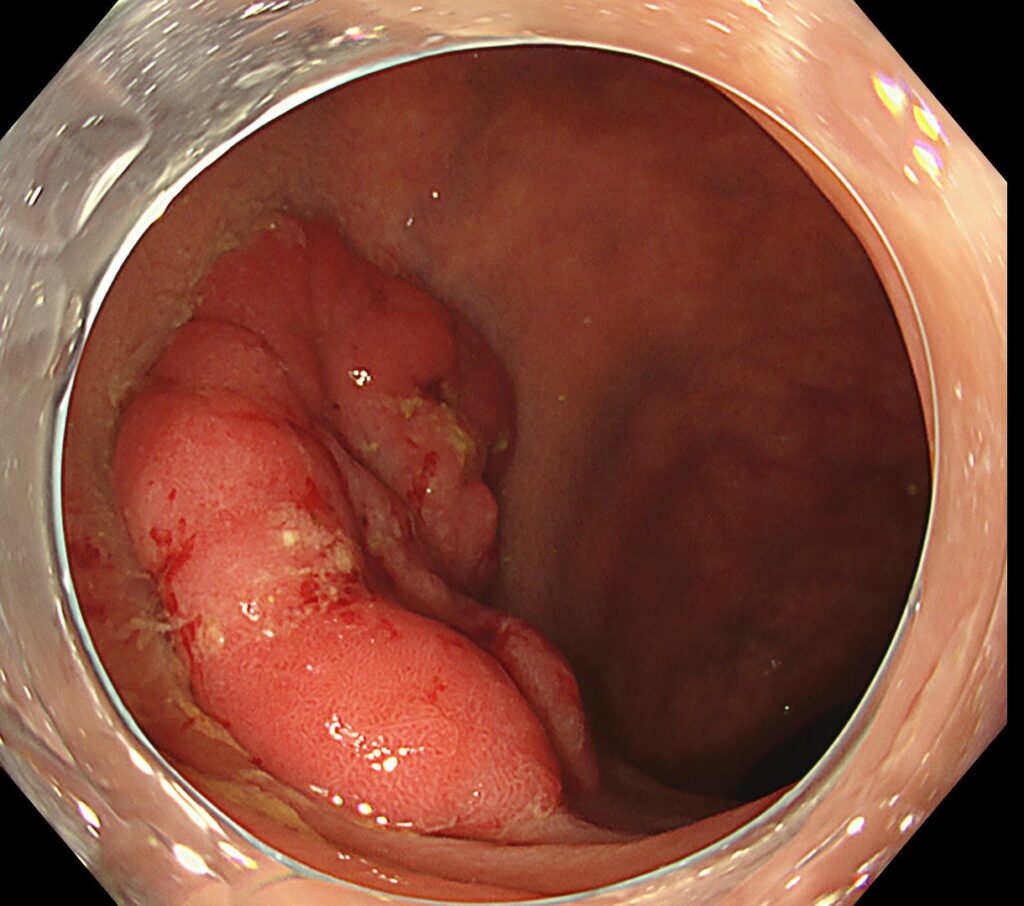

肛門から内視鏡を入れてすぐの下部直腸に、隆起性病変を認めます。

送気・脱気で腫瘍の硬さを確認してみると、浸潤癌らしき所見は認めず。

しっかり、空気を入れて、全体像を確認すると、内腔を1/4占めていることがわかります。